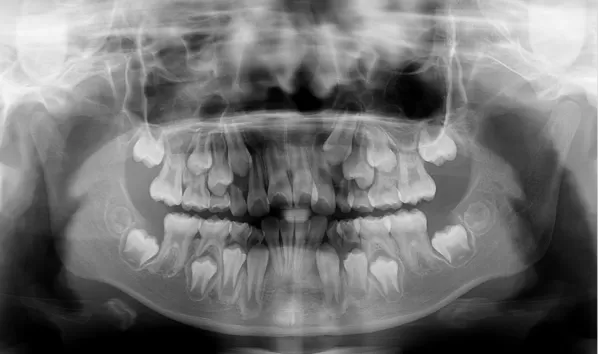

Rayons X avant le traitement

[Radiographie panoramique/Céphalogramme latéral]